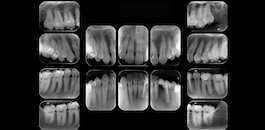

Periapical

Indicada para visualização detalhada das estruturas dento-alveolares.